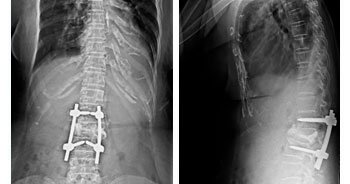

Surgery for Fractures of spine, disc prolapse and vertebroplasty are done on a regular basis in this hospital. Vertebroplasty is done for severely osteoporotic spine fractures. The team is headed by Dr.D.R.Shankar M.S., Mch.,(Neuro). Micro invasive spine surgery is also done here and the hospital has the good reputation for spine surgery. Our complication rate in spine surgery is one of the lowest in Chennai.

• SPINE SURGERY

Deformity Correction surgery is done for spine and mal united deformed long bones due to neglected or native treatment. Scientific methods and techniques are used in correction of spinal deformities, including congenital kyphoscoliosis, cubitus varus deformity of elbow, FFD correction and CTEV correction.